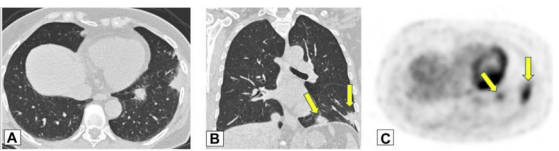

实变是OP病例中最常见的发现,发生于近75%的病例中,病变通常在双基底、支气管血管周围和/或外周。图1A为一名女性患者,右肺上叶周围实变,其曾因乳腺癌接受过放射治疗,并经活检证实为OP。图1B患者左肺下叶和舌叶周围实变,活检证实为继发于淋巴瘤化疗的OP。

图源:Chest, 2022, 162(1):156-178.图3A为71岁男性,2011年7月因劳力性呼吸困难就诊,胸片显示右肺上叶实变。图3B为2012年6月再次检查显示右肺上叶异常已消失,左肺出现广泛实变。图3C为2013年6月,左肺病变消失,但右肺下叶出现新的实变。这些发现是典型的OP游走性表现。图源:Chest, 2022, 162(1):156-178.图3所示患者胸部CT可见磨玻璃影伴小叶间隔增厚和铺路石征的游走灶(图4)。由此可见,OP的实变可以发生在肺的任何部位,边界清晰或模糊,呈游走性特点。图源:Chest, 2022, 162(1):156-178.OP的实变可以呈局灶性、多发性和弥漫性,也可以表现为结节或肿块。图5所示患者为70岁女性,COVID-19确诊9个月后出现持续气促,CT平扫图像显示支气管血管周围多灶性肿块样实变。在类固醇治疗后症状显著改善,实变消退,推测诊断为OP。图源:Chest, 2022, 162(1):156-178.实变常伴支气管充气征,可伴散在的磨玻璃样低密度或小实质结节。以主要的或完全的磨玻璃低密度为表现者较少见。图6A所示为一名有甲状腺乳头状癌病史的47岁男性患者碘131治疗4个月后的CT平扫图像,可见右肺上叶支气管血管周围磨玻璃影。PET/CT扫描显示磨玻璃影代谢增高(图6B)。CT平扫图像显示左肺上叶新出现的磨玻璃影(图6C)。支气管活检结果与OP相符。图源:Chest, 2022, 162(1):156-178.图7为一名71岁男性患者因使用胺碘酮导致SOP的CT平扫图像,可见左肺广泛磨玻璃影,小叶间隔增厚(铺路石征)。磨玻璃低密度影合并小叶间隔增厚可表现为铺路征。